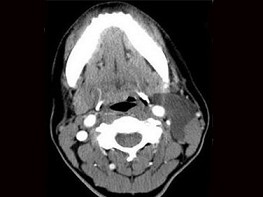

十產歲患者,女性,因頸前正中包塊3年入院,查體:頸前胸鎖乳突肌前緣上1/3外可觸及一圓形包塊,囊性,無壓痛,不隨吞咽上下活動。

6.CT檢查結果見下圖,本患者應考慮為  (    )

7.如果考慮為你所選的上述疾病,手術前應該完善下面那個檢查  (    )

正確答案:6.C;7.E